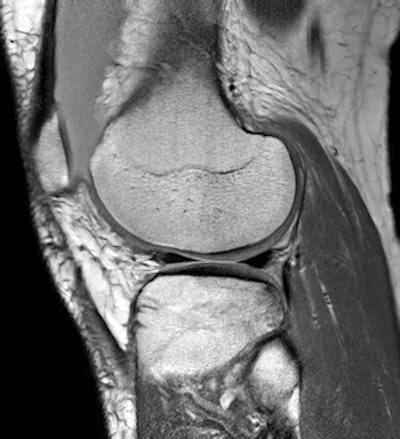

Musculoskeletal imaging is an area of special expertise among Colombian radiologists."It is an inexact science in which the higher the number of experts to join in the process, the better the result and lower the load of individual responsibility," he continued. "The radiologist is essential and irreplaceable in this regard."